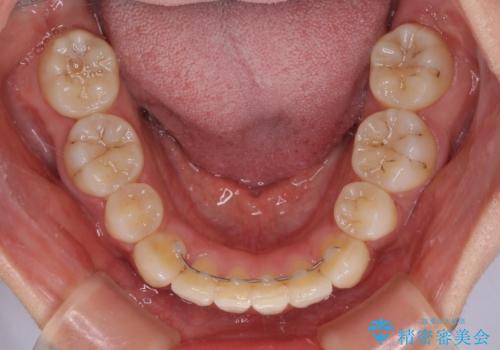

目安の装着時間である1日22時間をしっかりと実践してくださり、半年強という短期間で治療を終えることができました。